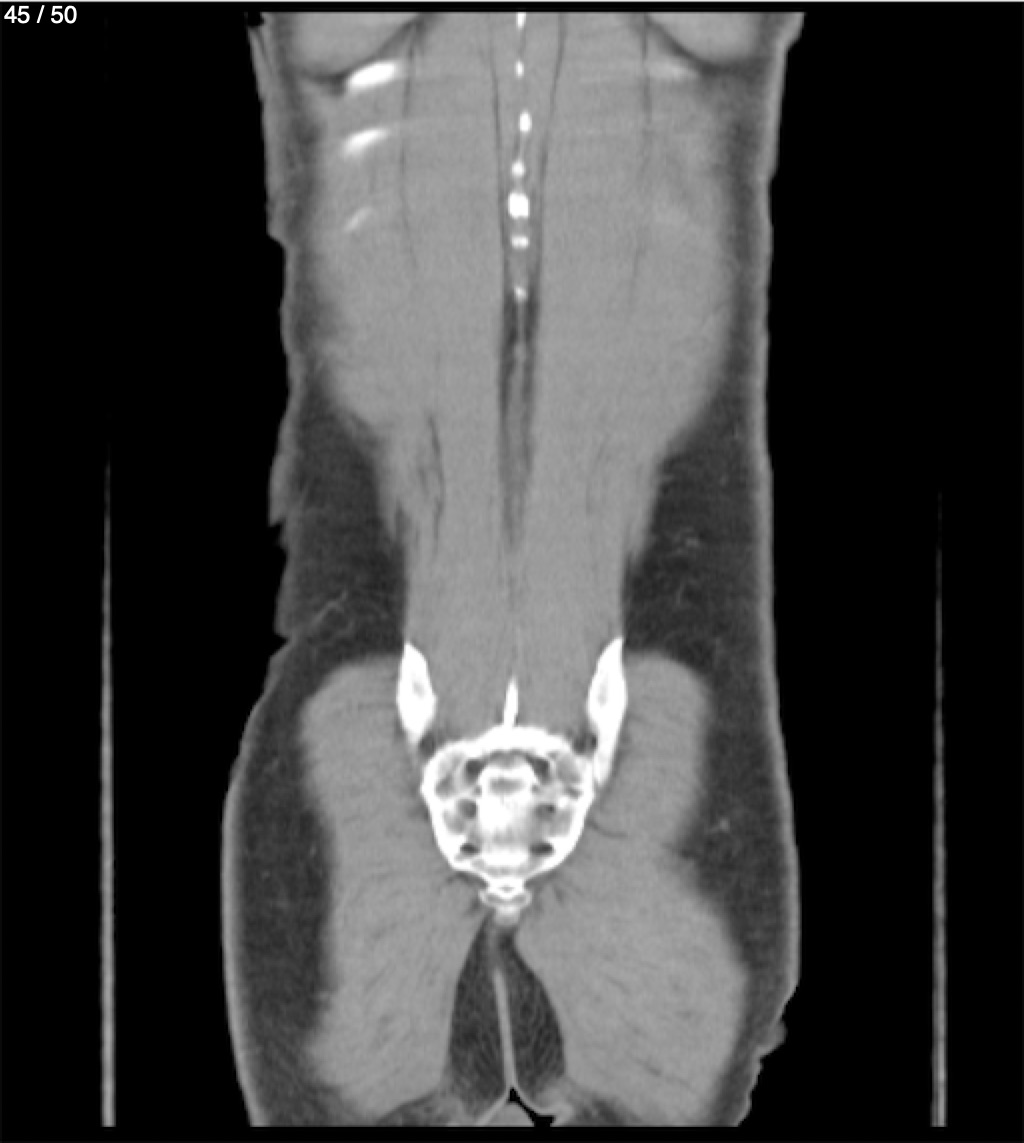

Alonso Victorio Ruiz 62A - T.C Abdomen Syc